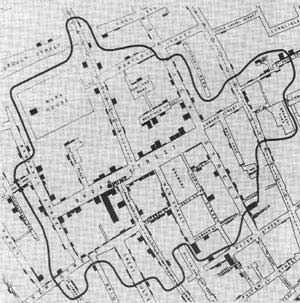

John Snow's map. Each bar represents a death at an address. The curve marks points at equal distance from the Broad Street pump and another pump.

Snow created an ingenious map that dramatically showed the geographic spread of deaths in the outbreak. Each bar on the graph represents a death at that address, showing as many as 18 people dying in particular households. This representation of the data shows that most of the deaths were tightly clustered in a specific area, crowded around the water pump at 40 Broad Street (now Broadwick Street) in Soho. Snow's research had led him to believe the Broad Street pump was the source of the disease, and this data backed up that theory. However, there were other pumps nearby, how could he show that it was most likely that this particular pump was the source?

His next ingenious step was to represent the time it took to travel to the Broad Street pump on his map and to calculate who was most likely to use each water pump in the area. Snow drew a curve on the map that marked the points where the Broad Street pump was at equal walking distance from neighbouring water pumps. If you live inside this curve the Broad Street pump is your nearest source of water. Almost all the deaths marked on the map lay inside this curve and anecdotal evidence explained the few cases that did not.